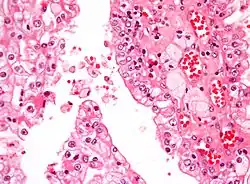

Micrograph showing the most common type of kidney cancer (clear cell renal cell carcinoma). H&E stain.

The most common type of kidney malignancy is renal cell carcinoma,[35] which is thought to originate from cells in the proximal convoluted tubule of the nephron.[15][36] Another type of kidney cancer although less common, is transitional cell cancer (TCC) or urothelial carcinoma of the renal pelvis.[37] The renal pelvis is the part of the kidney that collects urine and drains it into a tube called the ureter.[37] The cells that line the renal pelvis are called transitional cells, and are also sometimes called urothelial cells. The transitional/urothelial cells in the renal pelvis are the same type of cells that line the ureter and bladder. For this reason TCC of the renal pelvis is distinct from RCC and is thought to behave more like bladder cancer.[37] Other rare types of kidney cancers that can arise from the urothelial cells of the renal pelvis are squamous cell carcinoma and adenocarcinoma.[15]